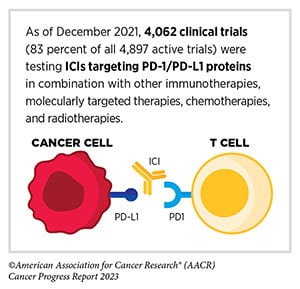

- The formulation of atezolizumab and hyaluronidase-tqjs (Tecentriq Hybreza) was new to the market in September. Atezolizumab is an immune checkpoint inhibitor (ICI), an immunotherapy that blocks the immune system’s natural “brakes” to help immune cells fight cancer. While it is approved for many indications as an intravenous infusion, its formulation with hyaluronidase-tqjs is injected subcutaneously, a much faster delivery process.

- Durvalumab (Imfinzi)—an ICI that targets the immune checkpoint protein PD-L1, which is expressed on tumors and other cells—has previously only been approved for patients with advanced, metastatic, or treatment-refractory cancers. In August, the FDA greenlit durvalumab for the treatment of early-stage, resectable NSCLC. The approval allows durvalumab to be given with platinum chemotherapy in the neoadjuvant setting (before surgery) then as a single-agent adjuvant therapy (after surgery) to prevent recurrence. Results from the phase III AEGEAN trial, which led to the approval, were presented at the AACR Annual Meeting 2023.

In the early days of ICI therapy, these drugs were primarily used to treat tumors that expressed certain checkpoint proteins. Eventually, researchers learned that some tumors were susceptible to ICIs in the absence of checkpoint protein expression. Molecular markers that may indicate strong expression of abnormal protein fragments—including mismatch repair deficiency (dMMR), high tumor mutational burden (TMB), and high microsatellite instability (MSI-H)—have been shown to also indicate susceptibility to ICIs. Therefore, several ICIs have been approved to treat tumors with dMMR, MSI-H, or high TMB regardless of checkpoint protein expression.

In recent years, researchers have found that some tumors without checkpoint protein expression respond to ICIs even in the absence of dMMR, MSI-H, and high TMB. This observation laid the groundwork for two new approvals this quarter.

- In September, pembrolizumab (Keytruda) plus chemotherapy was approved for the first-line treatment of patients with malignant pleural mesothelioma (MPM), a cancer of the chest cavity, with no biomarker requirements.

- Dostarlimab-gxly (Jemperli), an ICI targeting the same checkpoint pathway as pembrolizumab, also earned a biomarker-agnostic approval this quarter. In combination with the chemotherapies carboplatin and paclitaxel, dostarlimab-gxly is now approved for the treatment of adult patients with advanced or recurrent endometrial cancer. While it was approved in 2023 for such endometrial cancers characterized as dMMR or MSI-H, the current approval eliminates the biomarker requirements.